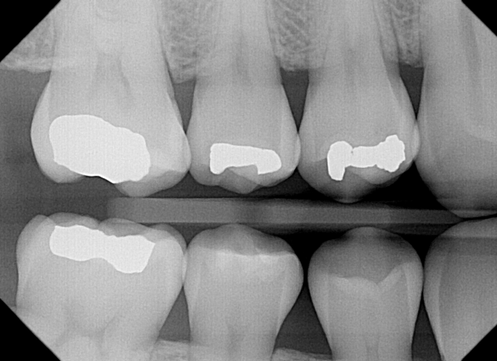

Oh, and by the way: When we restore teeth using treatments like fillings and crowns, we always use white (tooth-colored) materials. We are very good at hiding our work in plain sight, so you don't have to worry about leaving our office with a mouth full of old-school silver fillings.